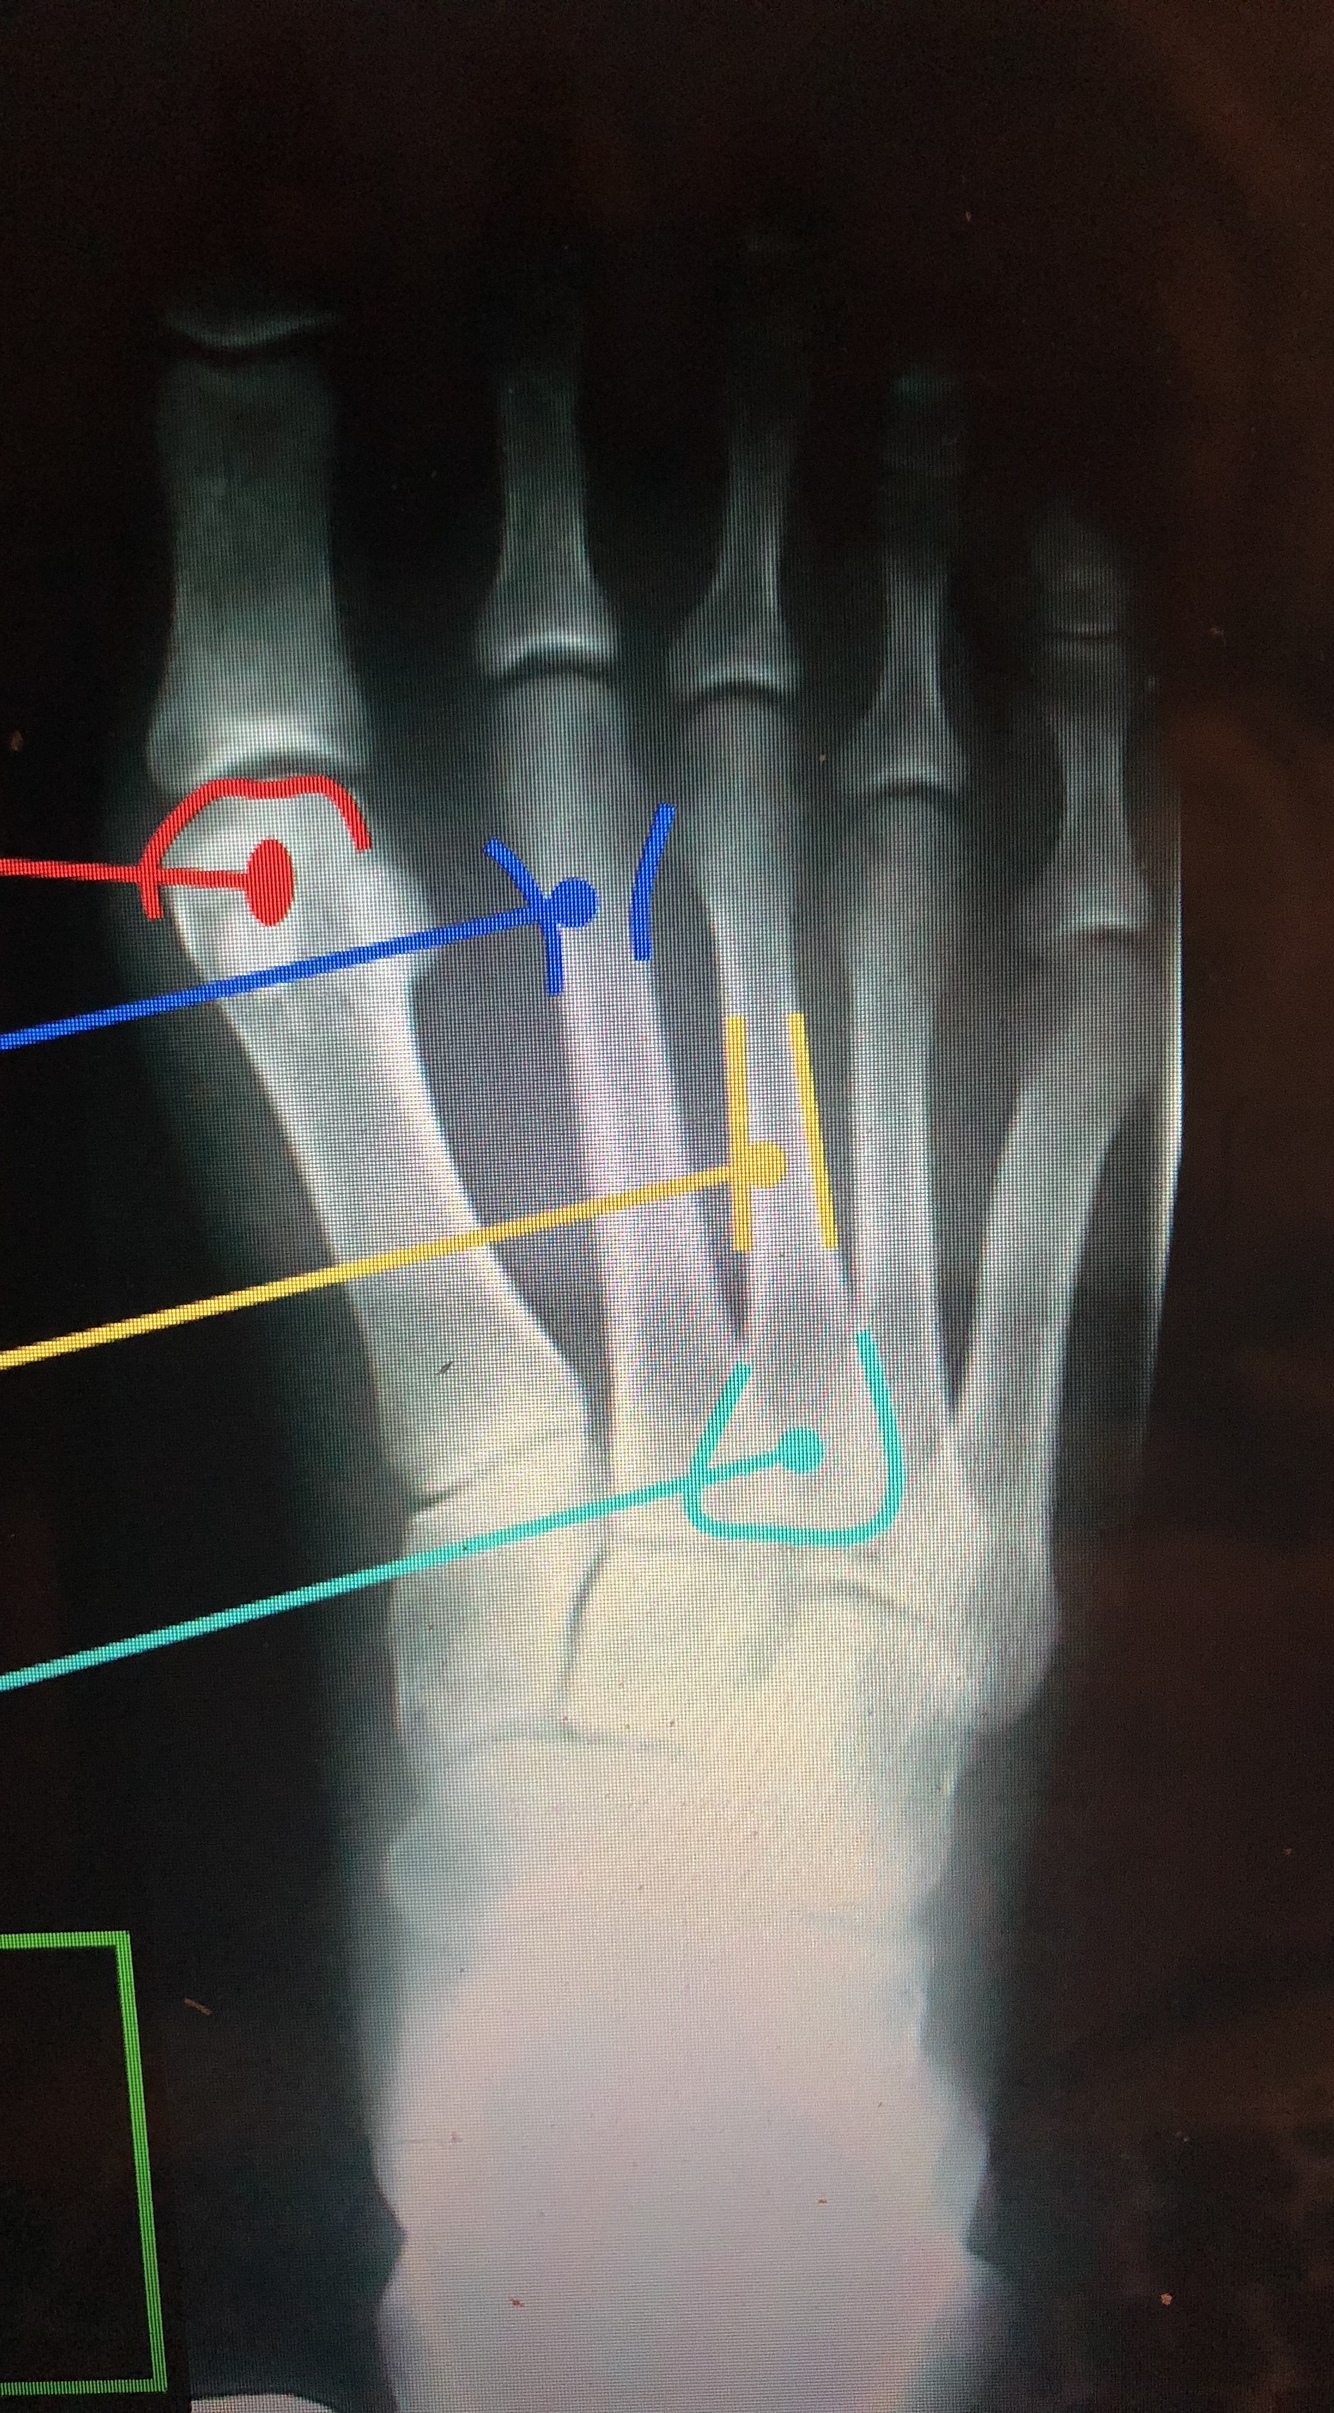

What is the red line?

head of 1st metatarsal

What is the dark blue line?

Neck of 2nd metatarsal

What is the yellow line?

Shaft of 3rd metatarsal

What is the light blue line?

base of the 3rd metatarsal

Styloid Process of the 5th Metatarsal

• Common fracture site in an inversion ankle sprain due to the pull of the peroneus brevis muscle